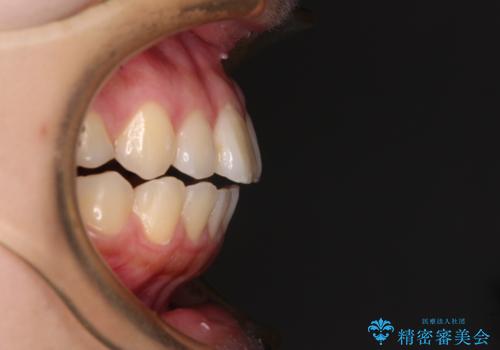

再矯正 開咬に後戻りした歯列をインビザラインで改善

- 矯正治療の後戻りを気にして来院された患者様です。

デコボコと上下前歯の隙間が気になるものの、しっかりと治療をしたいという意思はないとのことで、インビザラインの中でもアライナー数に制約のあるライトパッケージを用いて、治療できる範囲まで歯列を改善していくこととしました。

インビザラインは前歯部の開咬に効果的であることが多く、ライトパッケージにもかかわらず、十分満足のいく仕上がりとなりました。